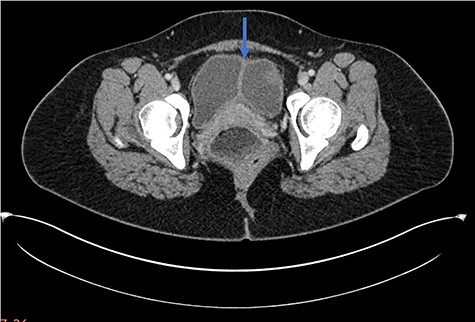

A 28-year-old woman presented to the emergency department with a 1-week history of abdominal pain, bloating and constipation. A computed tomography (CT) scan was performed, which demonstrated distension and a lead pipe appearance of the right colon suggesting a mild colitis (Fig. 1). The CT scan also demonstrated a duplicated segment of colon with a blind ending proximal limb (Figs 1 and 2), uterine didelphys (Fig. 2) and a duplicated bladder (Fig. 3). A subsequent magnetic resonance imaging scan demonstrated an 11 cm segment of thickened bowel with mucosal ulceration and surrounding hyperaemia confined to the duplicated colon. Sigmoidoscopy was performed and histology from the duplicated descending colon demonstrated mild active chronic colitis with crypt inflammation and associated abscesses without granuloma formation. The native colon had an unremarkable appearance. The patient was started on mesalazine and has had no further complaints of abdominal pain or bloating.

Axial CT scan demonstrating longitudinal sagittal septum giving rise to a duplicated bladder appearance.

Uterine didelphys results from incomplete Mullerian duct fusion and has varying reproductive outcomes. The incidence of Mullerian duct abnormalities ranges from 0.5 to 5%, with didelphic uteri representing 11% of uterine malformations [5]. The incidence is comparable between infertile and fertile cohorts [6], although the term delivery rate for patients with uterine didelphys is only 45% [7]. Duplication of the bladder is another rare clinical entity, arising from a complete sagittal septum of the bladder. Cases have been reported in the literature, although little is understood about the underlying aetiology [8, 9].